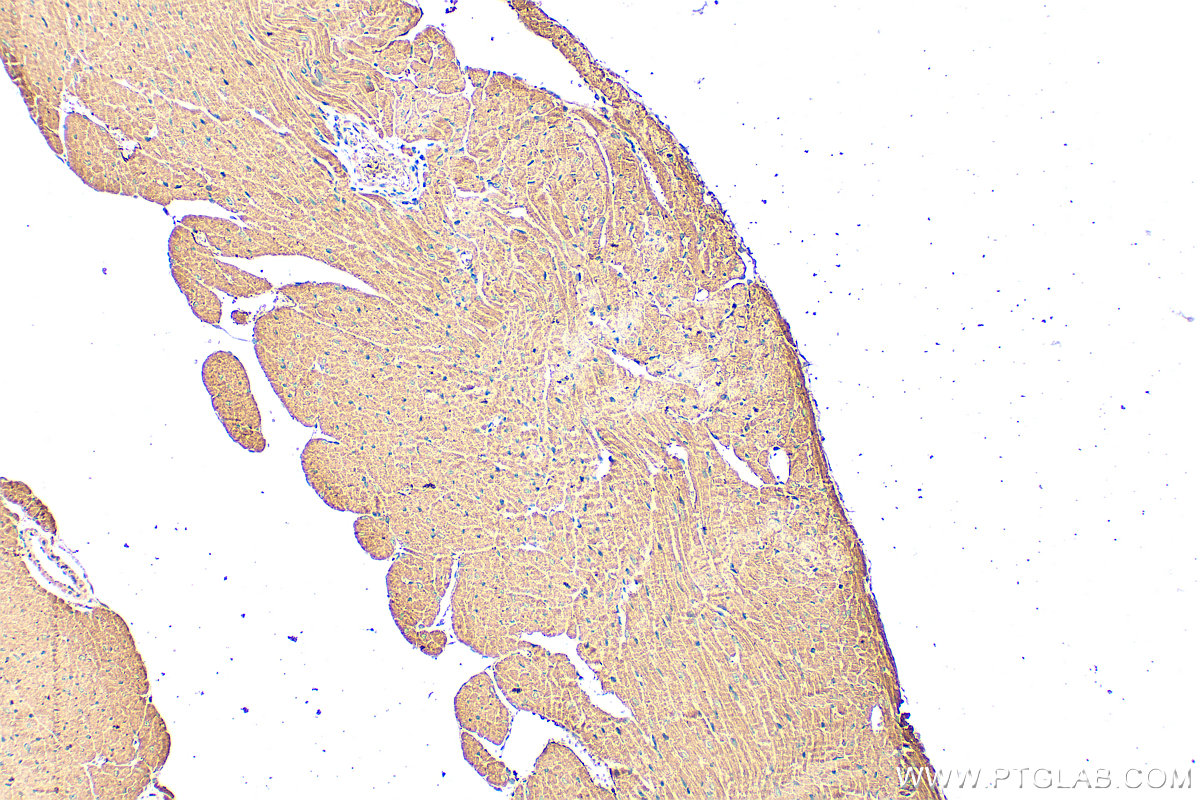

| Positive IHC detected in | mouse heart tissue Note: suggested antigen retrieval with TE buffer pH 9.0; (*) Alternatively, antigen retrieval may be performed with citrate buffer pH 6.0 |

25597-1-AP targets SLC10A5 in IHC, ELISA applications and shows reactivity with human, mouse samples.